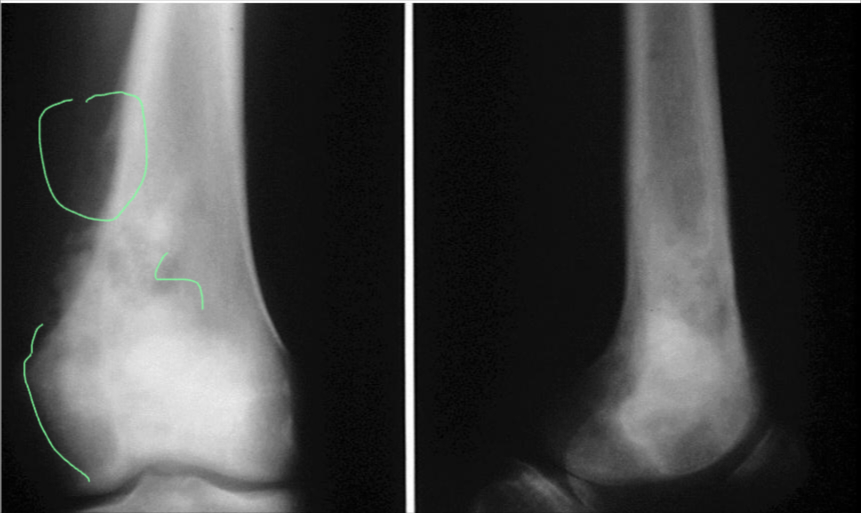

Aneurysmal Bone Cyst

site: Distal tibial

size: Involving most of distal part

matrix: Cortical expansion, radiolucent matrix, well defined, narrow zone of transition

soft tissue involvement: no peristeal reaction